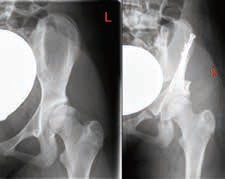

Triple-Beckenosteotomie nach Tönnis und Kalchschmidt

Bei älteren Kindern und Jugendlichen mit zunehmender Skelettreife sind die Flexibilität des Beckens und somit auch das Korrekturausmaß mit einer einfachen Beckenosteotomie nicht mehr ausreichend. Bei schweren Dysplasien wird nahe dem Acetabulum das Os ischii, das Os pubis und das Os ilium osteotomiert. Nun kann die Hüftpfanne in eine beliebige Richtung geschwenkt werden. Ziel ist eine bessere Überdachung im mechanisch bedeutsamen ventralen und lateralen Anteil. Im Anschluss erfolgt eine Stabilisierung mittels Schraubenosteosynthese im Bereich des Os ilium 3031 (Abb. 10). Allerdings sollte dabei eine Überkorrektur vermieden werden. Das beste Outcome konnte für CE-Winkel nach Wiberg zwischen 25° und 35° gezeigt werden 32.